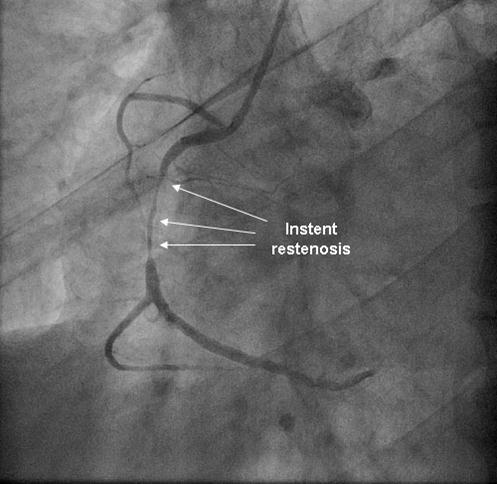

Coronary angiography was again performed. On injections into the left system, collaterals to the distal RCA were demonstrated (figure 1), arising from the left circumflex coronary artery (CX). Injections into the RCA demonstrated tight in-stent restenosis, (figure 2) and a drug eluting stent was successfully implanted. After the angioplasty, injections into the RCA were seen to retrogradely fill the CX (figure 3). The suspicion arose that maybe the left coronary artery had been inadvertently damaged during angiography, so the left coronary was again cannulated and injections performed, demonstrating entirely normal left main and CX arteries. However, the collateral flow that had previously been demonstrated from the CX to the RCA was no longer apparent. On review of the previous angiogram, it was noted that the RCA retrogradely filled the CX despite the original significant stenosis (figure 4). In essence, it became apparent that the bidirectional filling of the RCA from the CX and vice versa was in fact a direct continuity between the vessels and not collaterals, as free flow was noted from the RCA to the CX even when both arteries were completely patent.

Figure 2.Instent restenosis in proximal RCA